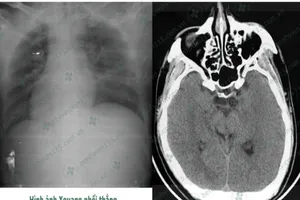

Tài xế hôn mê sâu khi lái xe chỉ vì quên ăn sáng